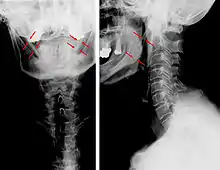

| Anteroposterior and lateral radiographs of cervical spine showing ossification of the stylohyoid ligament on both sides | |

Radiograph, lateral view showing elongated stylohyoid process and stylohyoid ligament ossification

Radiograph, lateral view showing elongated stylohyoid process and stylohyoid ligament ossification Radiograph, lateral view showing joint-like formation in ossified stylohyoid ligament

Diagnosis is suspected when a patient presents with the symptoms of the classic form of "Eagle syndrome" e.g. unilateral neck pain, sore throat or tinnitus. Sometimes the tip of the styloid process is palpable in the back of the throat. The diagnosis of the vascular type is more difficult and requires an expert opinion. One should have a high level of suspicion when neurological symptoms occur upon head rotation. Symptoms tend to be worsened on bimanual palpation of the styloid through the tonsillar bed. They may be relieved by infiltration of lidocaine into the tonsillar bed. Because of the proximity of several large vascular structures in this area this procedure should not be considered to be risk free.

Imaging is important and is diagnostic. Visualizing the styloid process on a CT scan with 3D reconstruction is the suggested imaging technique.[12] The enlarged styloid may be visible on an orthopantogram or a lateral soft tissue X ray of the neck.